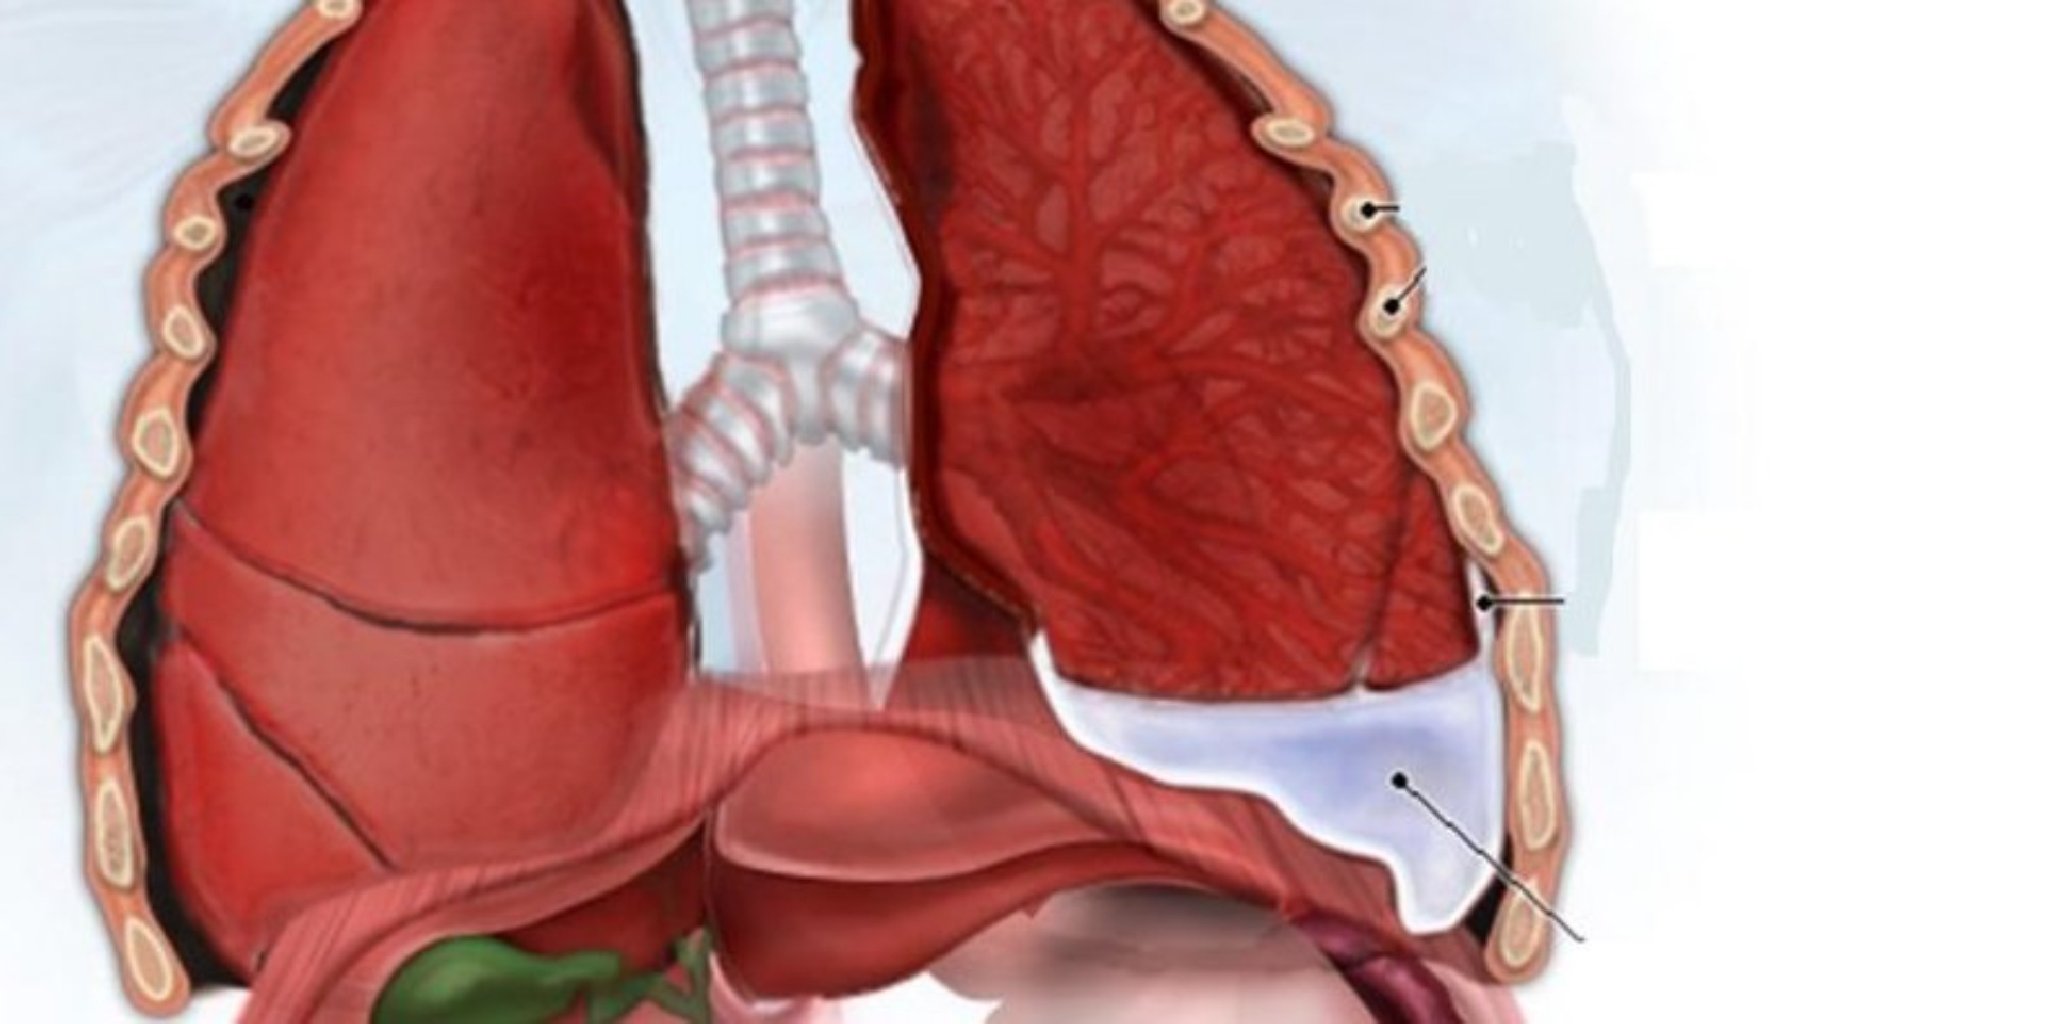

Plevritin səbəbləri arasında aşağıdakılar yer ala bilər: Viral və Bakterial İnfeksiyalar: Viru ...

Plevritin Səbəbləri Plevritin müxtəlif səbəbləri ola bilər: İnfeksiyalar: Bakterial və ya v ...

Prosesin Gedişi Sinə ultrasəs müayinəsi zamanı, xəstə adətən arxaya uzanır və ya oturur. Ultrason ...

Prosesin Amacı Ağciyər ponksiyonunun birkaç temel amacı vardır: Təşhis: Plevral efüzyonun ( ...